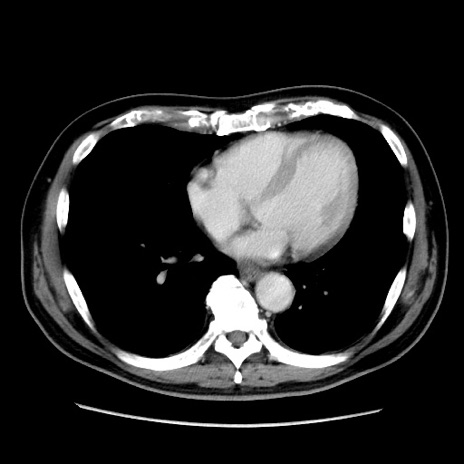

症例16(横断像)

【症例】 70歳代男性

【主訴】 腹痛、嘔吐

【現病歴】 約1ヶ月前より間欠的に腹痛と嘔吐あり、当院消化器内科を受診したところCTで多発する肝臓のLDAを指摘され、精査中であった。以降は消化器症状は安定していたが、2日前より嘔気と腹痛があり、同日より排便・排ガスが消失した。改善認めず、 本日、救急外来を受診した。

【既往歴】 大腸ポリープ切除後。

【身体所見】意識清明・会話良好、BT 36.3℃、BP 127/80mmHg、 P 80bpm、腹部:膨満あり、平坦・軟、上腹部正中および下腹部正中に圧痛あり、反跳痛なし、筋性防御なし。

【データ】WBC 7200、CRP 0.77